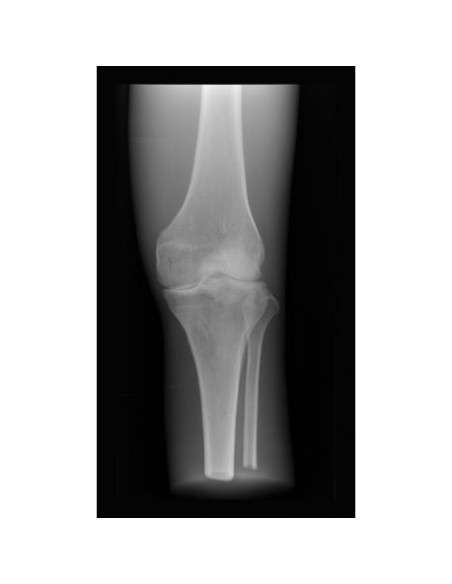

Simulador Radiológico - Rodilla - Opaco - Erler Zimmer 7255

Este indispensable simulador de radiología médica ofrece la oportunidad única de tomar radiografías de partes individuales del cuerpo una y otra vez.

El maniquí contiene huesos humanos reales y permite tomar radiografías reales.

Los huesos están incrustados en material plástico recubierto de un color opaco para ocultar las estructuras internas.

El simulador radiológico de rodilla está hecho a mano y es único.

Puede variar en color y forma.

Debido a la alta tecnología utilizada en su producción, puede haber decoloración y grietas en el interior.

Esto está relacionado con la producción y no con una falta de calidad